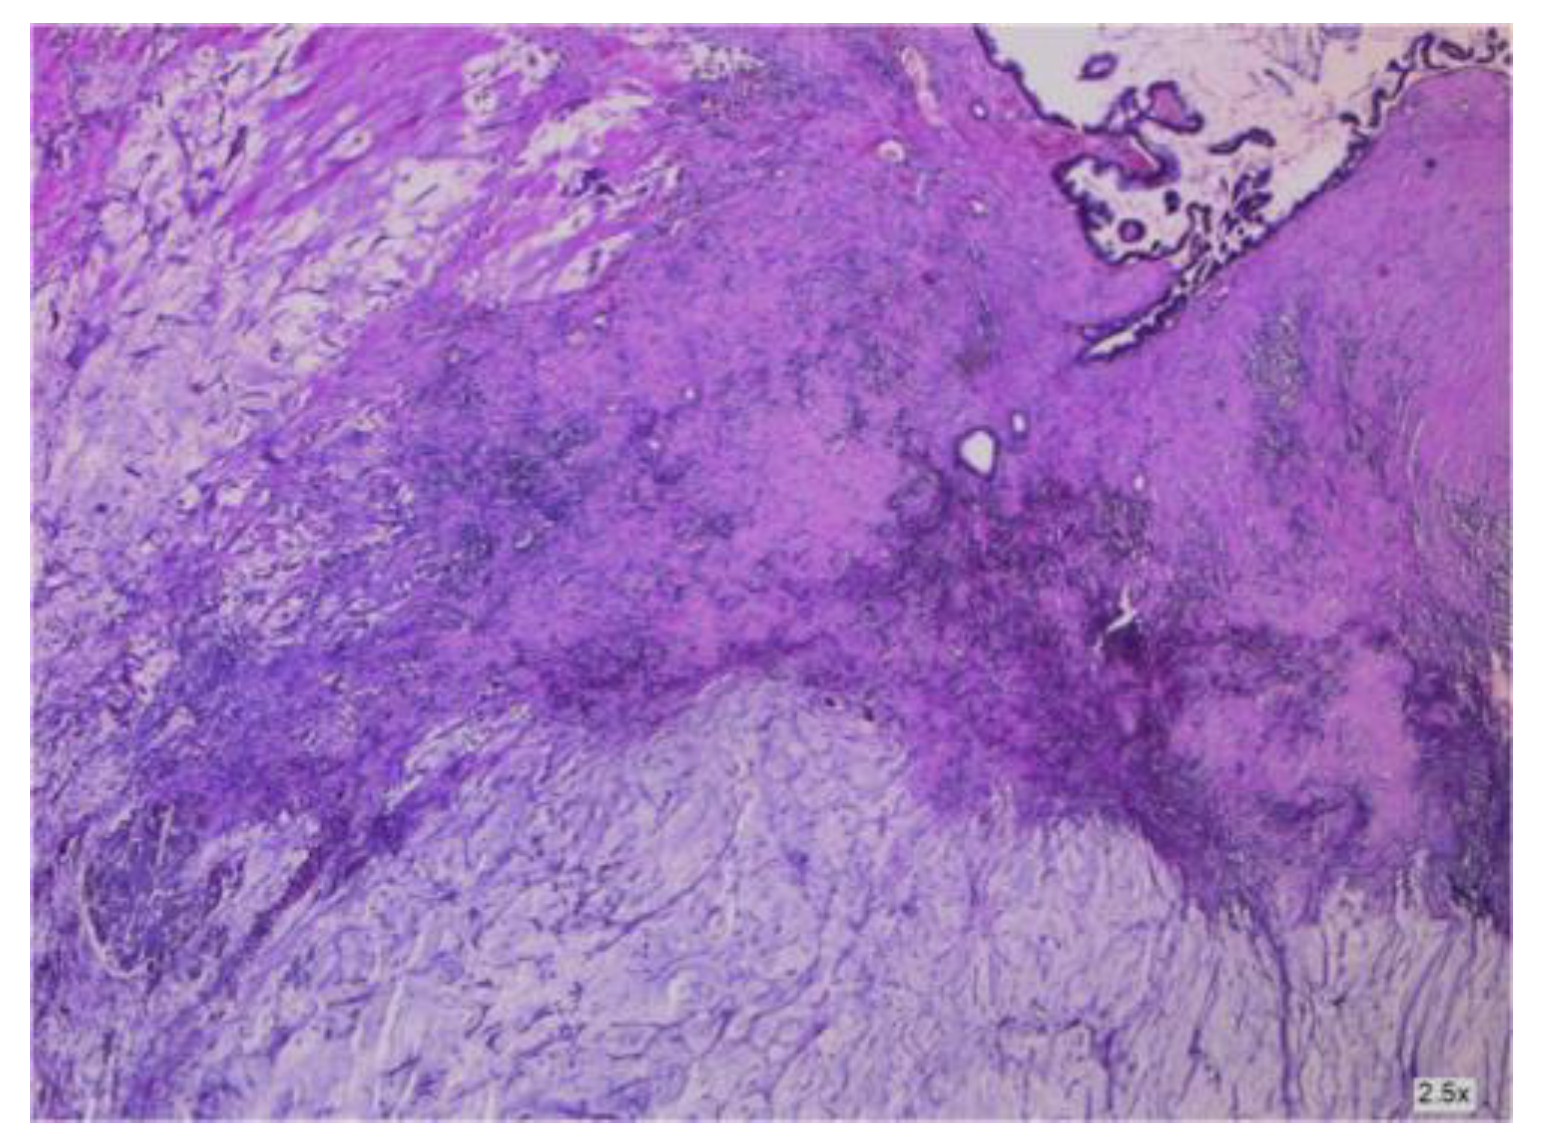

3.1.1. Mucinous Cystadenoma

3.2.2. Clinical and Pathology Findings